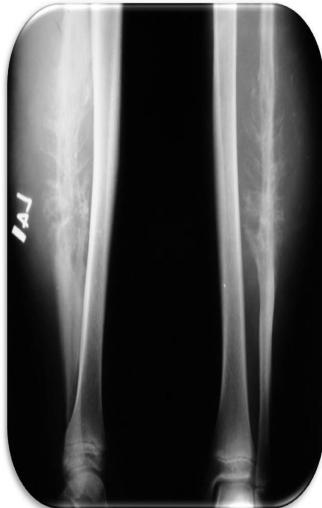

Aneurysmal Bone Cyst

site: Distal tibial

size:  Involving most of distal part

matrix: Cortical expansion, radiolucent matrix, well defined, narrow zone of transition

soft tissue involvement:  no peristeal reaction